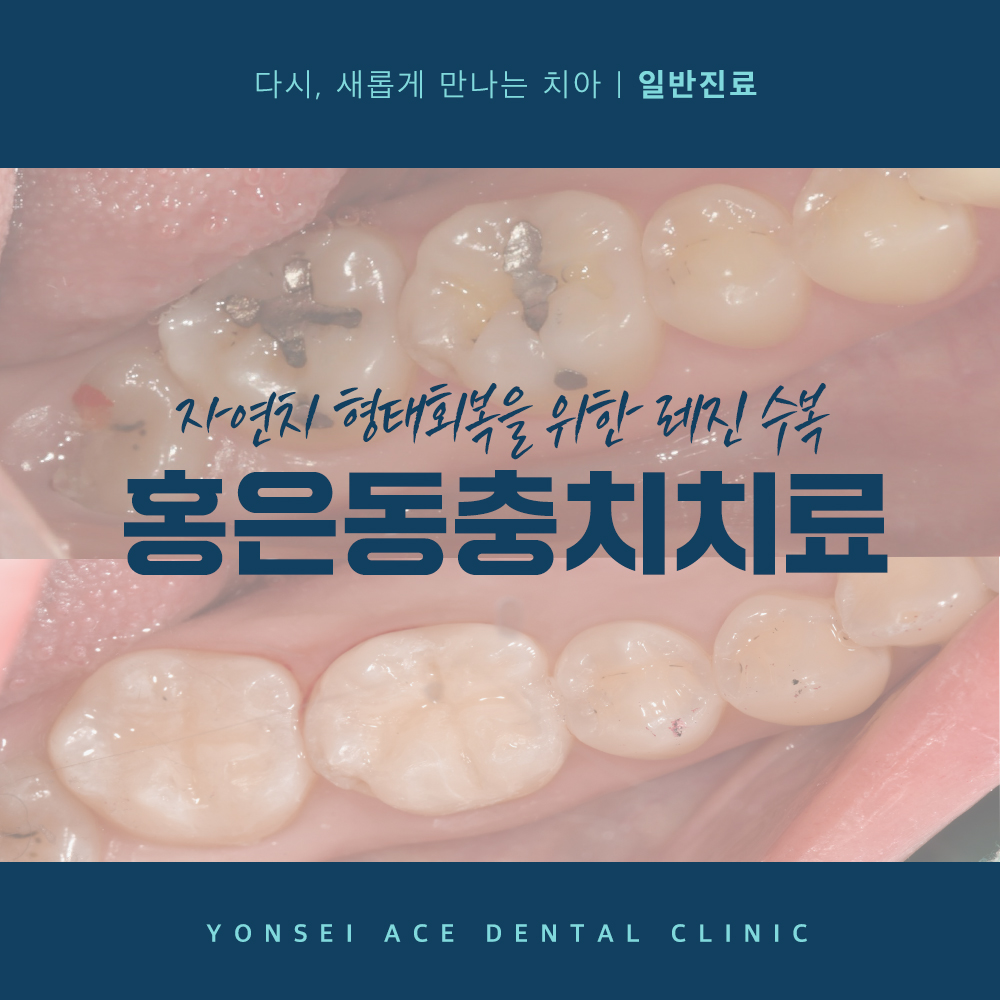

위 환자분은 구강에 오래된 아말감으로

구치부가 수복되어 있는 상태였는데요.

검진 차 내원하셨을 때 아말감 주변과

하방으로 이차 우식이 발생되어 있었고,

아말감이 부분적으로 탈락되어 있었어요.

충치치료를 위해 먼저 수복되어 있던 아말감을

제거하였으며, 다행히 부위가 깊고 넓지 않아

레진으로 치료를 진행할 수 있었어요.

치료 마무리 전, 후 사진이에요.🔍

인접하고 있는 자연치아들과 유사한 색상을 띄며

형태를 회복한 모습을 보실 수 있어요.